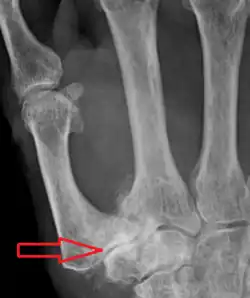

Trapeziometacarpal osteoarthritis (TMC OA) is, also known as osteoarthritis at the base of the thumb, thumb carpometacarpal osteoarthritis, basilar (or basal) joint arthritis, or as rhizarthrosis.[3][1][2] This joint is formed by the trapezium bone of the wrist and the metacarpal bone of the thumb. This is one of the joints where most humans develop osteoarthritis with age.[4] Osteoarthritis is age-related loss of the smooth surface of the bone where it moves against another bone (cartilage of the joint).[3][5] In reaction to the loss of cartilage, the bones thicken at the joint surface, resulting in subchondral sclerosis. Also, bony outgrowths, called osteophytes (also known as "bone spurs"), are formed at the joint margins.[6]

TMC OA is diagnosed based on symptoms and signs.[8] Radiographs can confirm the diagnosis and the severity of TMC OA. Other diagnoses in this region include scaphotrapezial trapezoid arthritis and first dorsal compartment tendinopathy (De Quervain syndrome) although these are usually easy to distinguish.

TMC OA severity was classified by Eaton and Littler which can be simplified as follows:[21][22]

- Osteophytes, < 2 mm in diameter, are present. (usually adjacent to the volar or dorsal facets of the trapezium)

Stage 3:

- Osteophytes, > 2 mm in diameter, are present (usually adjacent to the volar and dorsal facets of the trapezium)

- Slight joint space narrowing